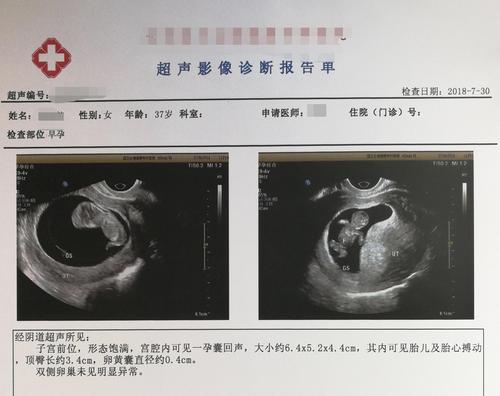

2018年7月,小滚珠的诊断报告。肚子里的孩子第一次有了清晰的人形。受访者供图